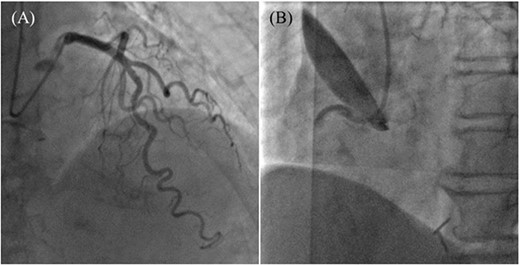

An 85-year-old woman with a history of hypertension and cerebral infarction presented to the emergency department of another hospital with the complaint of temporary loss of consciousness (LOC). Dehydration was suspected to be the cause of LOC; however, CAG was performed to confirm the reason for the mild elevation in creatine kinase and D-dimer levels. While the left coronary system was intact (Fig. 1A), the coronary dissection spread retrogradely from the right sinus of Valsalva to the ascending aorta after injecting contrast into the right coronary artery (RCA). The RCA was completely occluded at the proximal part, and no collateral flow into the RCA was observed (Fig. 1B). Electrocardiography revealed previously undetected ST elevation in leads II, III, and aVF and reciprocal ST depression in leads I, aVL, and V4–6 (Fig. 2). Contrast-enhanced CT confirmed aortic dissection which was localized in the ascending aorta (Fig. 3A). Additionally, RCA occlusion at the proximal portion was suspected (Fig. 3B). The patient was transferred to our institute for further management of the aortocoronary dissection. On arrival, the patient was alert and oriented with close to normal vital signs. Echocardiography showed a normal left ventricular ejection fraction with preserved RV function; however, severe hypokinesis of the inferior wall was noted. Moreover, as the hemodynamic status of the patient gradually deteriorated in the emergency department, we decided to perform an emergency surgery.

Preoperative electrocardiography. ST elevation in leads II, III, and aVF, and reciprocal ST depression in leads I, aVL, and V4-6 were detected.